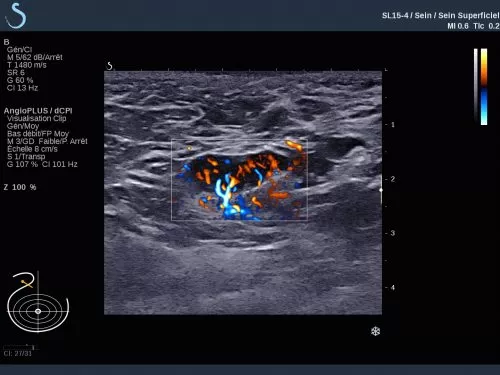

The Aixplorer Ultimate ultrasound unique capabilities of Shearwave Elastography, are going to be presented in the workshop which will be held on 29/9/2018, during the ultrasound – elastography workshop.

Find out how SWE can help you increase the sensitivity of the ultrasound exam, the biopsy predictive value, and how a DCIS can be upgraded to IDC.